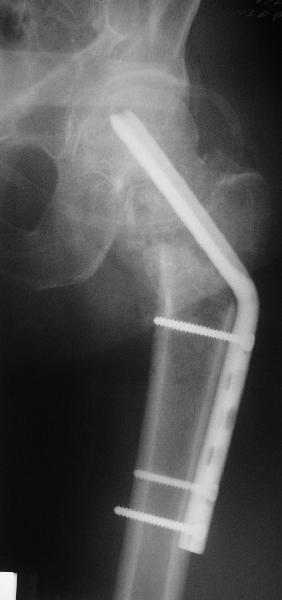

[Ortho] Нелеченный перелом шейки бедра

Приветствую всех. Спасибо за активное участие в обсуждении. Выбрали вариант с остеотомией.

Снимки в приложении.

Имя     : get_image2.jpg